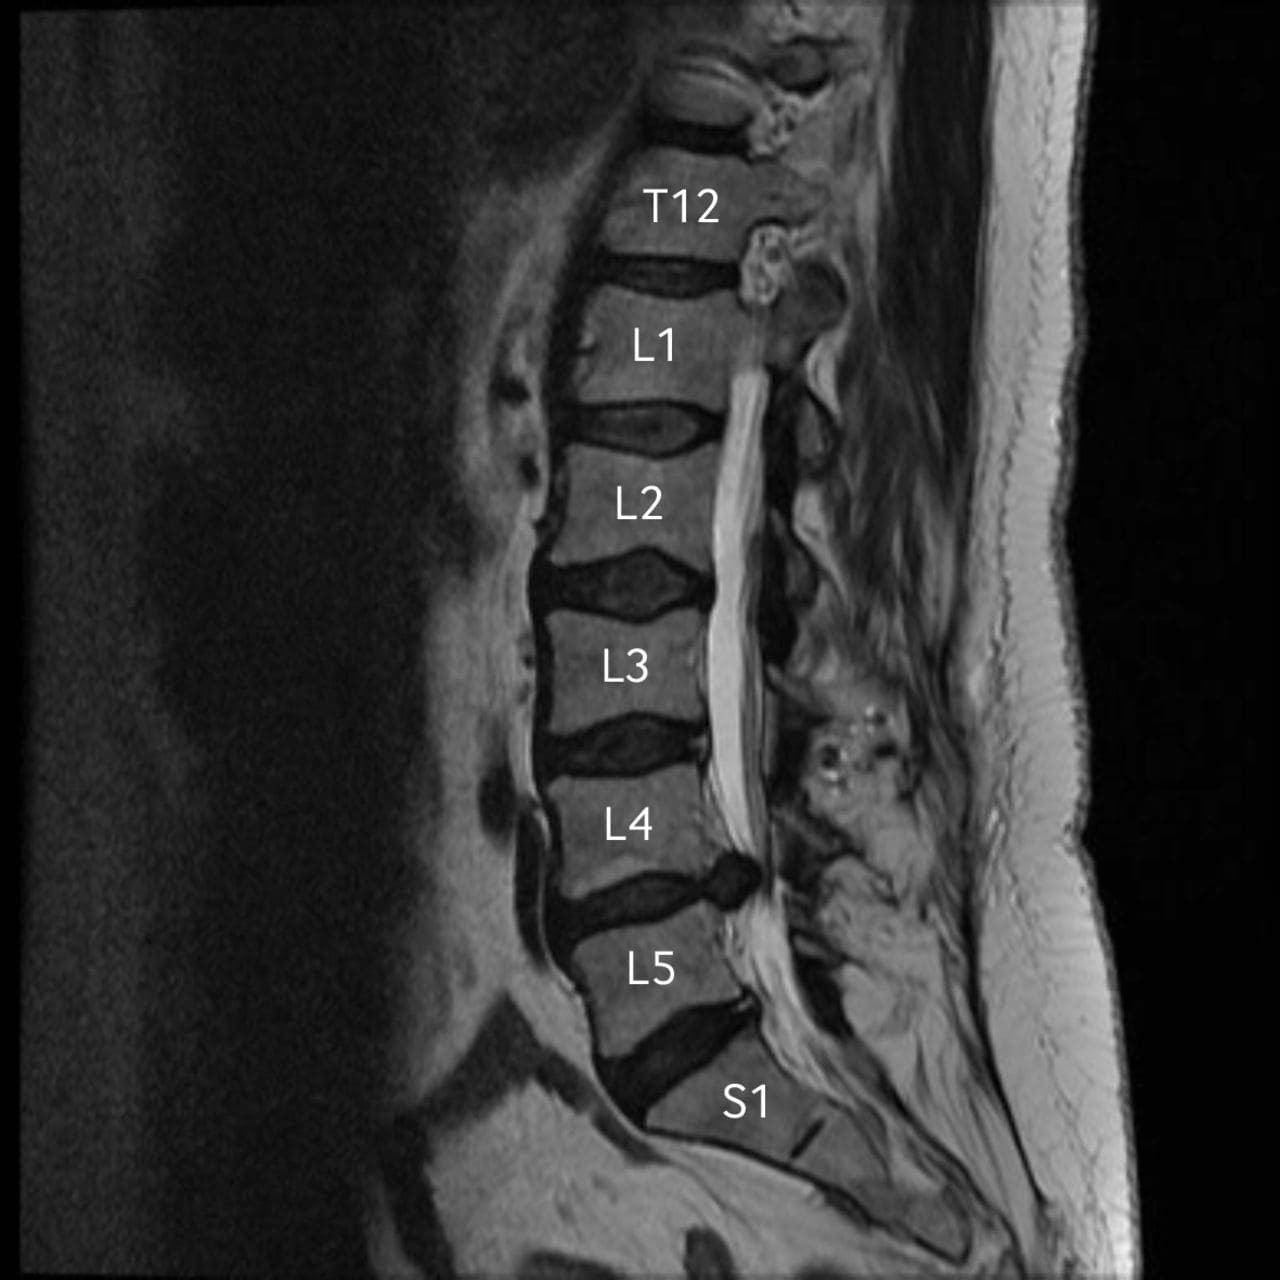

КТ-протрузии дисков: Визуализация и классификация